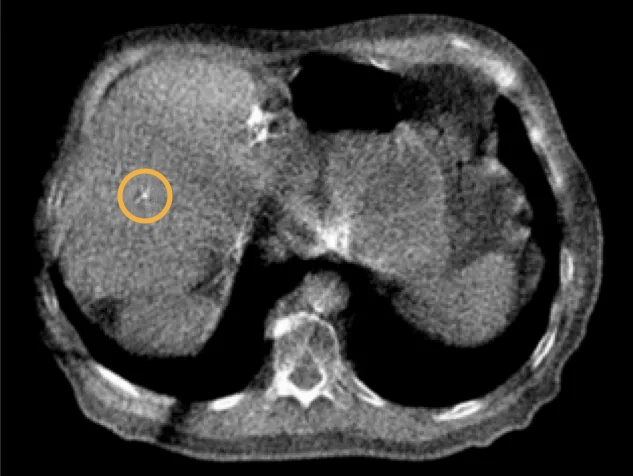

The image shows a ball shaped 0.4×20 mm Gold Anchor used for positioning of a liver SBRT patient. The MVCT image was acquired with the TomoTherapy® Hi Art® treatment system immediately prior the treatment.

Visible on MVCT